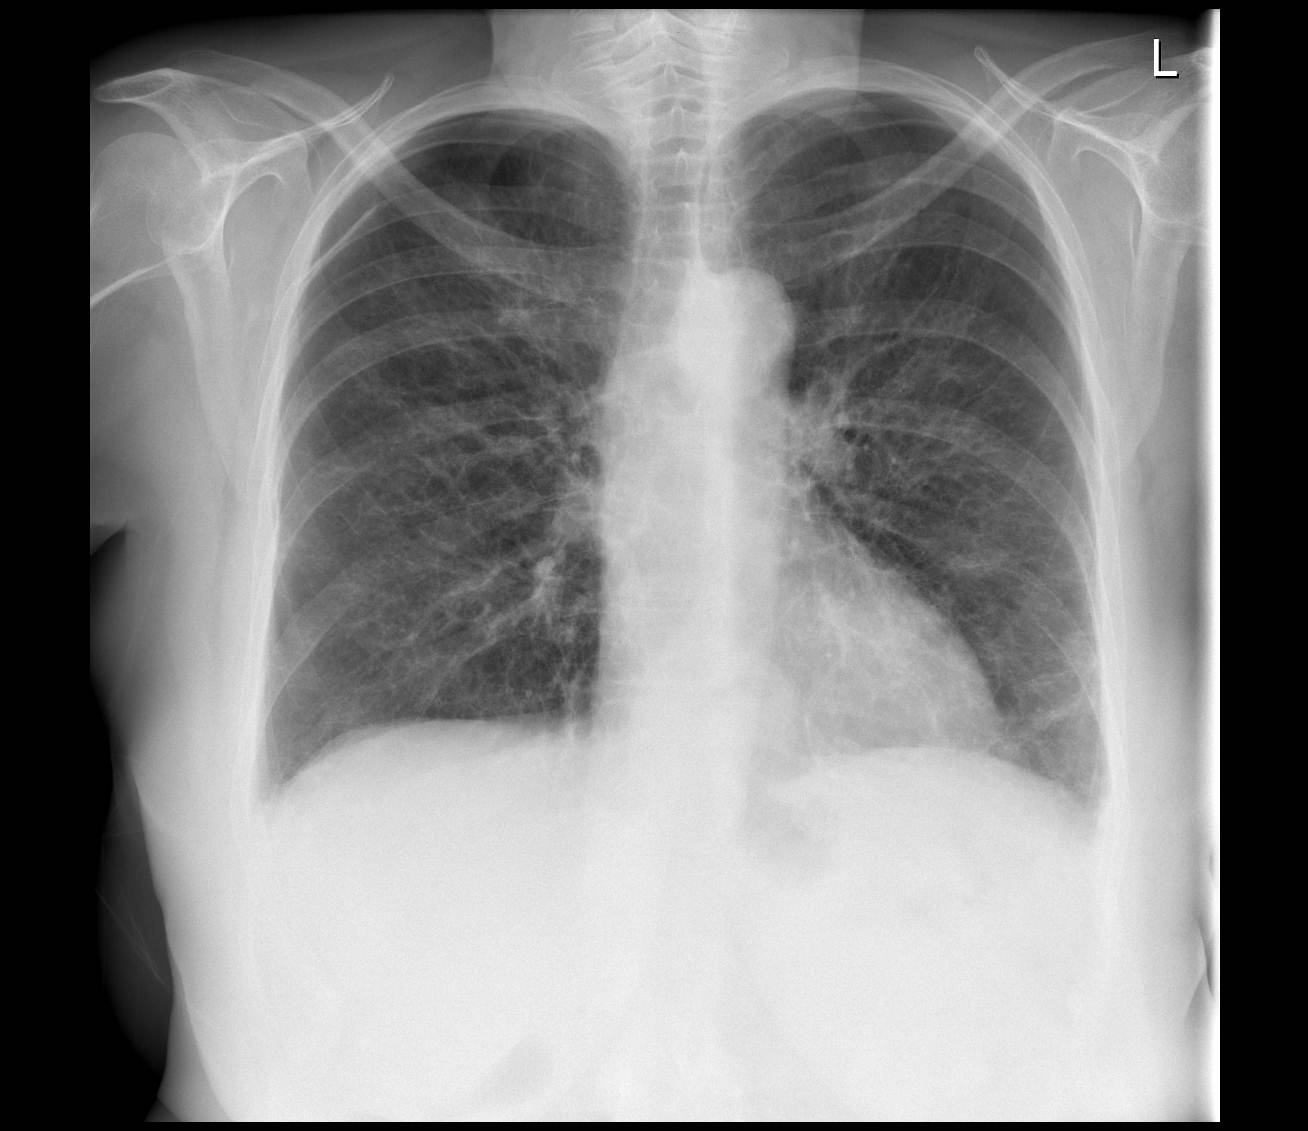

Снимок крупозной пневмонии.

Крупозная пневмония

Воспалительные процессы крупозного характера отличаются тем, что проходят в несколько стадий. В самом начале развития этой пневмонии, когда появляются первые типичные симптомы, на снимках еще не наблюдается каких-либо изменений или же они носят неспецифический характер. Вот список того, что можно заметить на этом этапе:

- локальное небольшое усиление лёгочного сосудистого рисунка;

- небольшое расширение корня легкого с той стороны, где произошло поражение;

- нормальная прозрачность полей или же её небольшое снижение.

Как несложно догадаться, подобные симптомы нередко пропускаются специалистами, не имеющими достаточного опыта. Также нередко это относят к проявлениям бронхита. Но через несколько дней на снимках можно заметить явное поражение легких:

- прозрачность легочного поля сильно снижается;

- происходит резкое уменьшение воздушности, а также появляются затемнения недостаточно интенсивного характера;

- корень легкого на той стороне, где произошло воспаление, расширяется.

Специалисты отмечают, что крупозная пневмония всегда сопровождается реакцией плевры. В области плевральной щели происходит затемнение при появлении выпота.